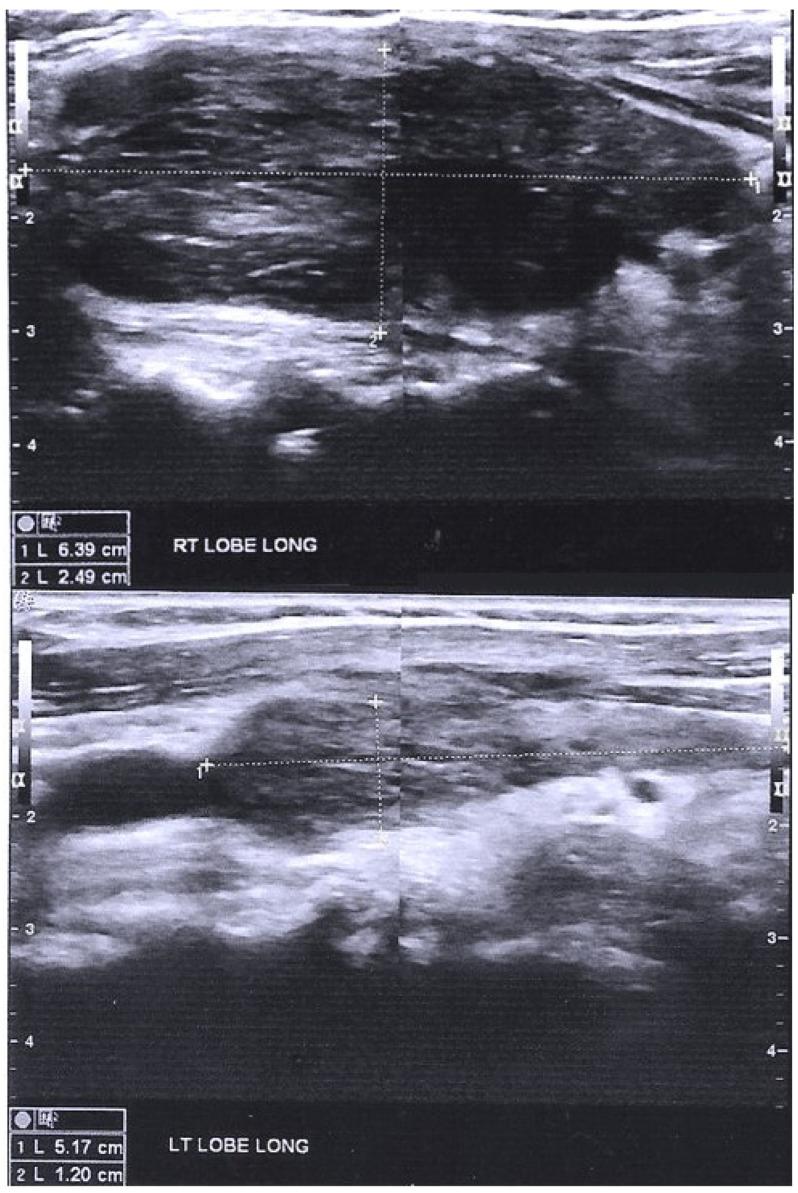

SARS-CoV-2 infection and vaccination have been associated with autoimmune thyroid dysfunctions. Autoimmune/inflammatory syndrome induced by adjuvants (ASIA) and molecular mimicry have been referred to as potential causes. Such a case has not been reported in immunocompromised end-stage renal disease (ESRD) patients. Herein we present two dialysis patients with no previous history of thyroid disease who developed immune mediated thyroid disorders after BNT162b mRNA vaccine against SARS-CoV-2. The first patient is a 29-year-old man on hemodialysis diagnosed with Grave's disease four months post-vaccination and the second one is a 67-year-old female on peritoneal dialysis who developed Hashimoto's thyroiditis two months post-vaccination. Grave's disease is uncommon in dialysis patients, whereas Hashimoto's thyroiditis has a higher incidence in this population. Time proximity in both cases suggests potential causality. To our knowledge, this is the first report of de novo immune-mediated thyroid disorders in dialysis patients following vaccination against SARS-CoV-2.